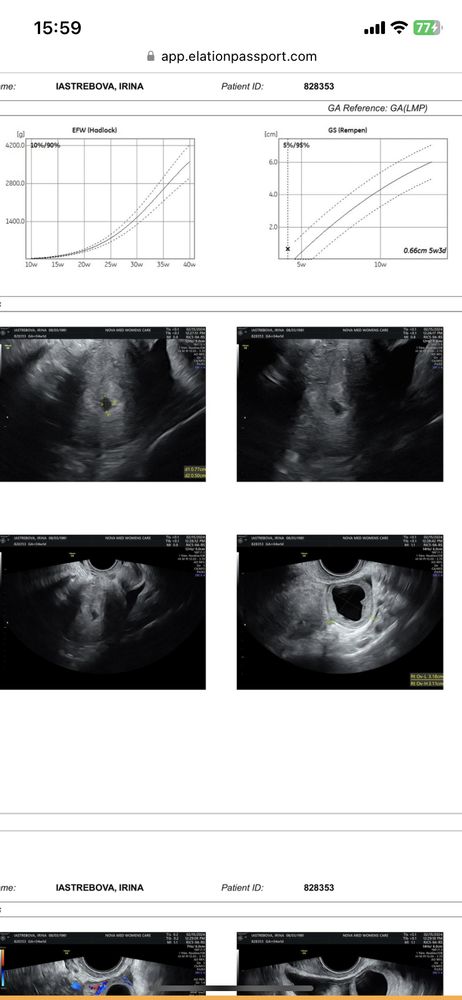

Есть же плодное яйцо: gs rempen это оно. Соответствует сроку. Всё ок.

Ну тут написано, что 0,66 см плодное яйцо, что соответствует 5 неделям и 3 дням

Ирина Богданова, и как я поняла ЖТ на правом яичнике

15.02.2024

Ольга, да желтое тело на правом я ,вы абсолютно правы ,спасибо я даже не прочитала запаниковала

Написано "предположительно плодное яйцо или свободная жидкость". Я бы переделала, может, узист такой.